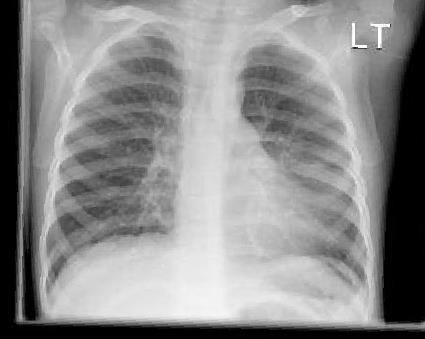

A 2-year-old girl is brought to an urgent care clinic by her guardian due to a harsh, barking cough and noticeable difficulty breathing that started overnight. Her guardian reports she's had a low-grade fever and mild nasal congestion for the past two days. On examination, she presents with inspiratory stridor and is using accessory muscles to breathe, though her oxygen saturation is stable at 94% on room air. A rapid point-of-care chest X-ray is performed, revealing characteristic subglottic narrowing. Considering the clinical presentation and radiographic findings, what is the most likely underlying etiology and the appropriate initial pharmacologic intervention?